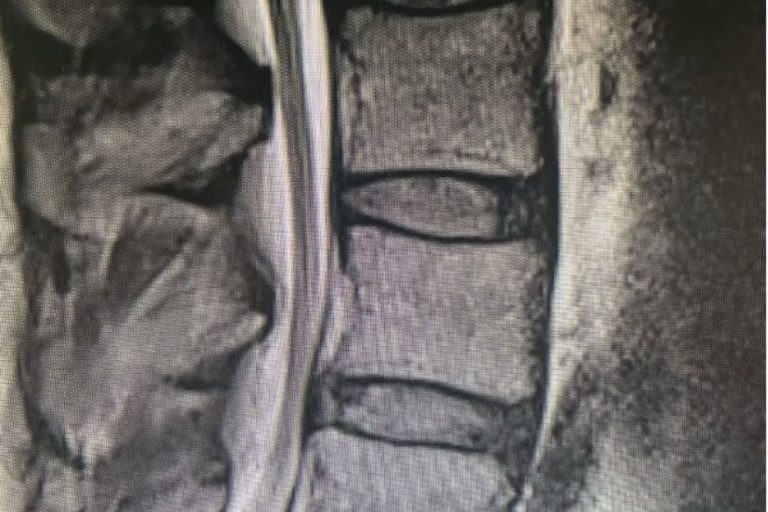

Two-Level Cervical Disc Replacement: Is Disc Arthroplasty the Right Choice for Your Neck Pain?

Cervical total disc replacement or disc arthroplasty is becoming an increasingly popular procedure. Now, the cervical disc replacements are even approved for doing 2 levels, as in this recent case that I performed. Is it right for you? Many things are possible in spine surgery but only a few things are most appropriate for you…